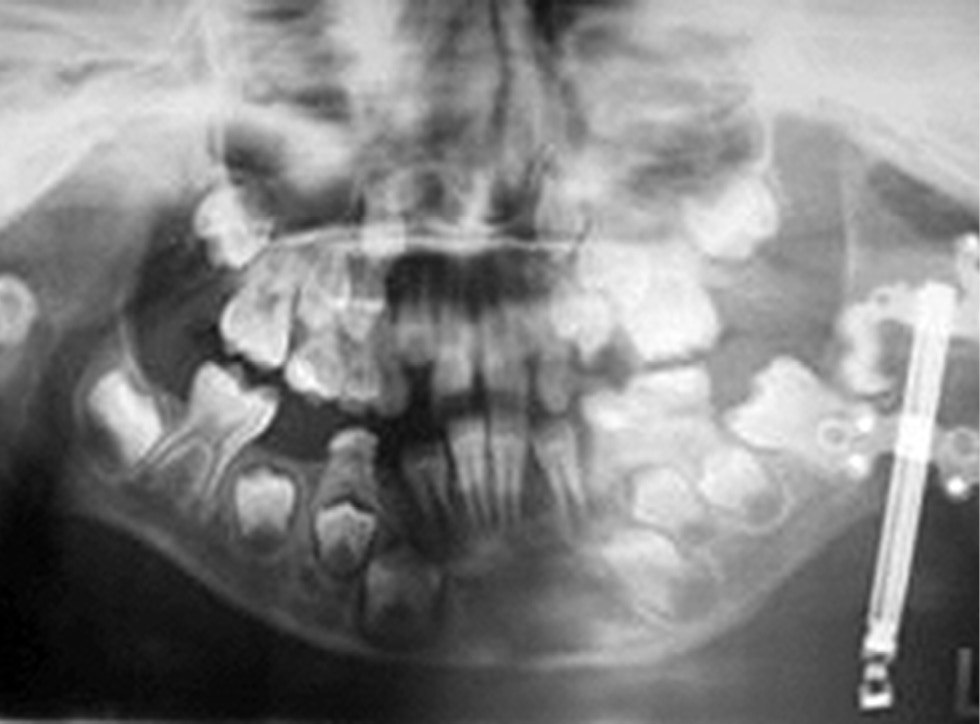

При анализе рентгенограмм, сделанных в период ретенции во всех группах, определялись характерные признаки оссификации новообразованных регенератов независимо от темпа дистракции между фрагментами; при этом наиболее зрелым и рентгенологически качественным представлялся регенерат с темпом непрерывной дистракции 2 мм в сутки (рис. 2).

Рис. 2. Рентгенограмма регенерата, полученного с темпом непрерывной дистракции 2 мм в сутки.

Fig. 2. X-ray of the regenerate obtained with a continuous distraction rate of 2 mm per day.